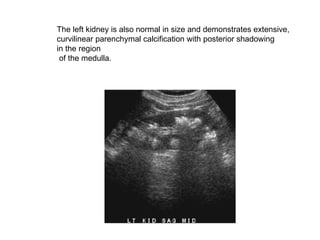

The left kidney is also normal in size and demonstrates extensive,  curvilinear parenchymal calcification with posterior shadowing  in the region of the medulla.